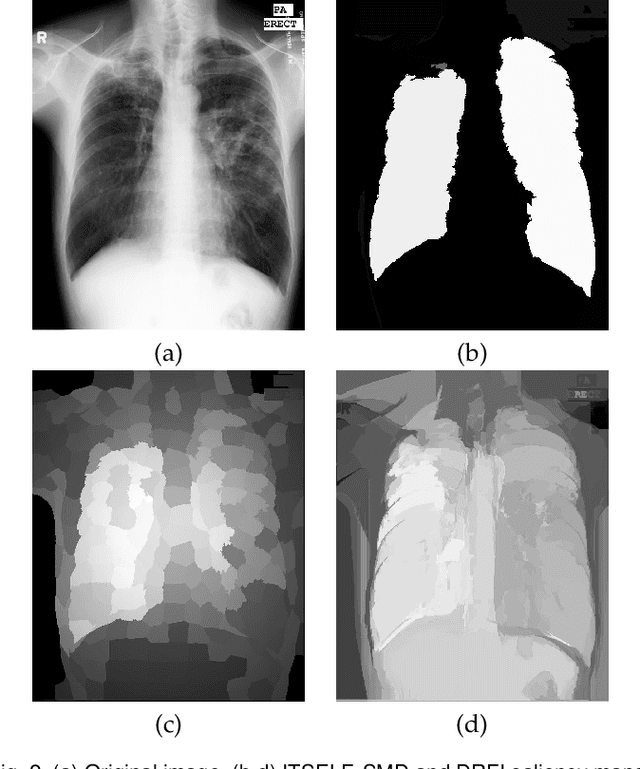

Abstract:Saliency object detection estimates the objects that most stand out in an image. The available unsupervised saliency estimators rely on a pre-determined set of assumptions of how humans perceive saliency to create discriminating features. By fixing the pre-selected assumptions as integral part of their models, these methods cannot be easily extended for specific settings and different image domains. We then propose an superpixel-based ITerative Saliency Estimation fLexible Framework (ITSELF) that allows any number of user-defined assumptions to be added to the model when required. Thanks to recent advancement on superpixel segmentation algorithms, saliency-maps can be used to improve superpixel delineation. By combining a saliency-based superpixel algorithm to a superpixel-based saliency estimator, we propose a novel saliency/superpixel self-improving loop to iteratively enhance saliency maps. We compared ITSELF to two state-of-the-art saliency estimators on five metrics and six datasets, four of which are composed of natural-images, and two of biomedical-images. Experiments show that our approach is more robust than the compared methods, presenting competitive results on natural-image datasets and outperforming them on biomedical-image datasets.